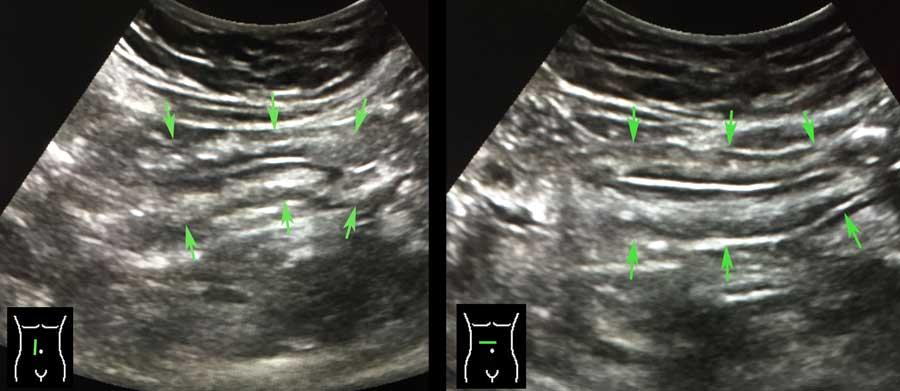

Ở người béo phì, mạc treo chứa nhiều mỡ và có thể được quan sát như một cấu trúc nhiều lớp, dẹt, dễ nén ép.

Trong một mặt phẳng, điều này có thể mô phỏng hình ảnh thành ruột dày lên (các mũi tên trong hình bên trái).

Xoay đầu dò 90 độ (hình bên phải), cấu trúc này ngay lập tức được nhận ra là một cấu trúc phẳng (các mũi tên).

Ở rìa mạc treo mỡ, có thể quan sát thấy nhu động rõ rệt ở hai quai ruột non.